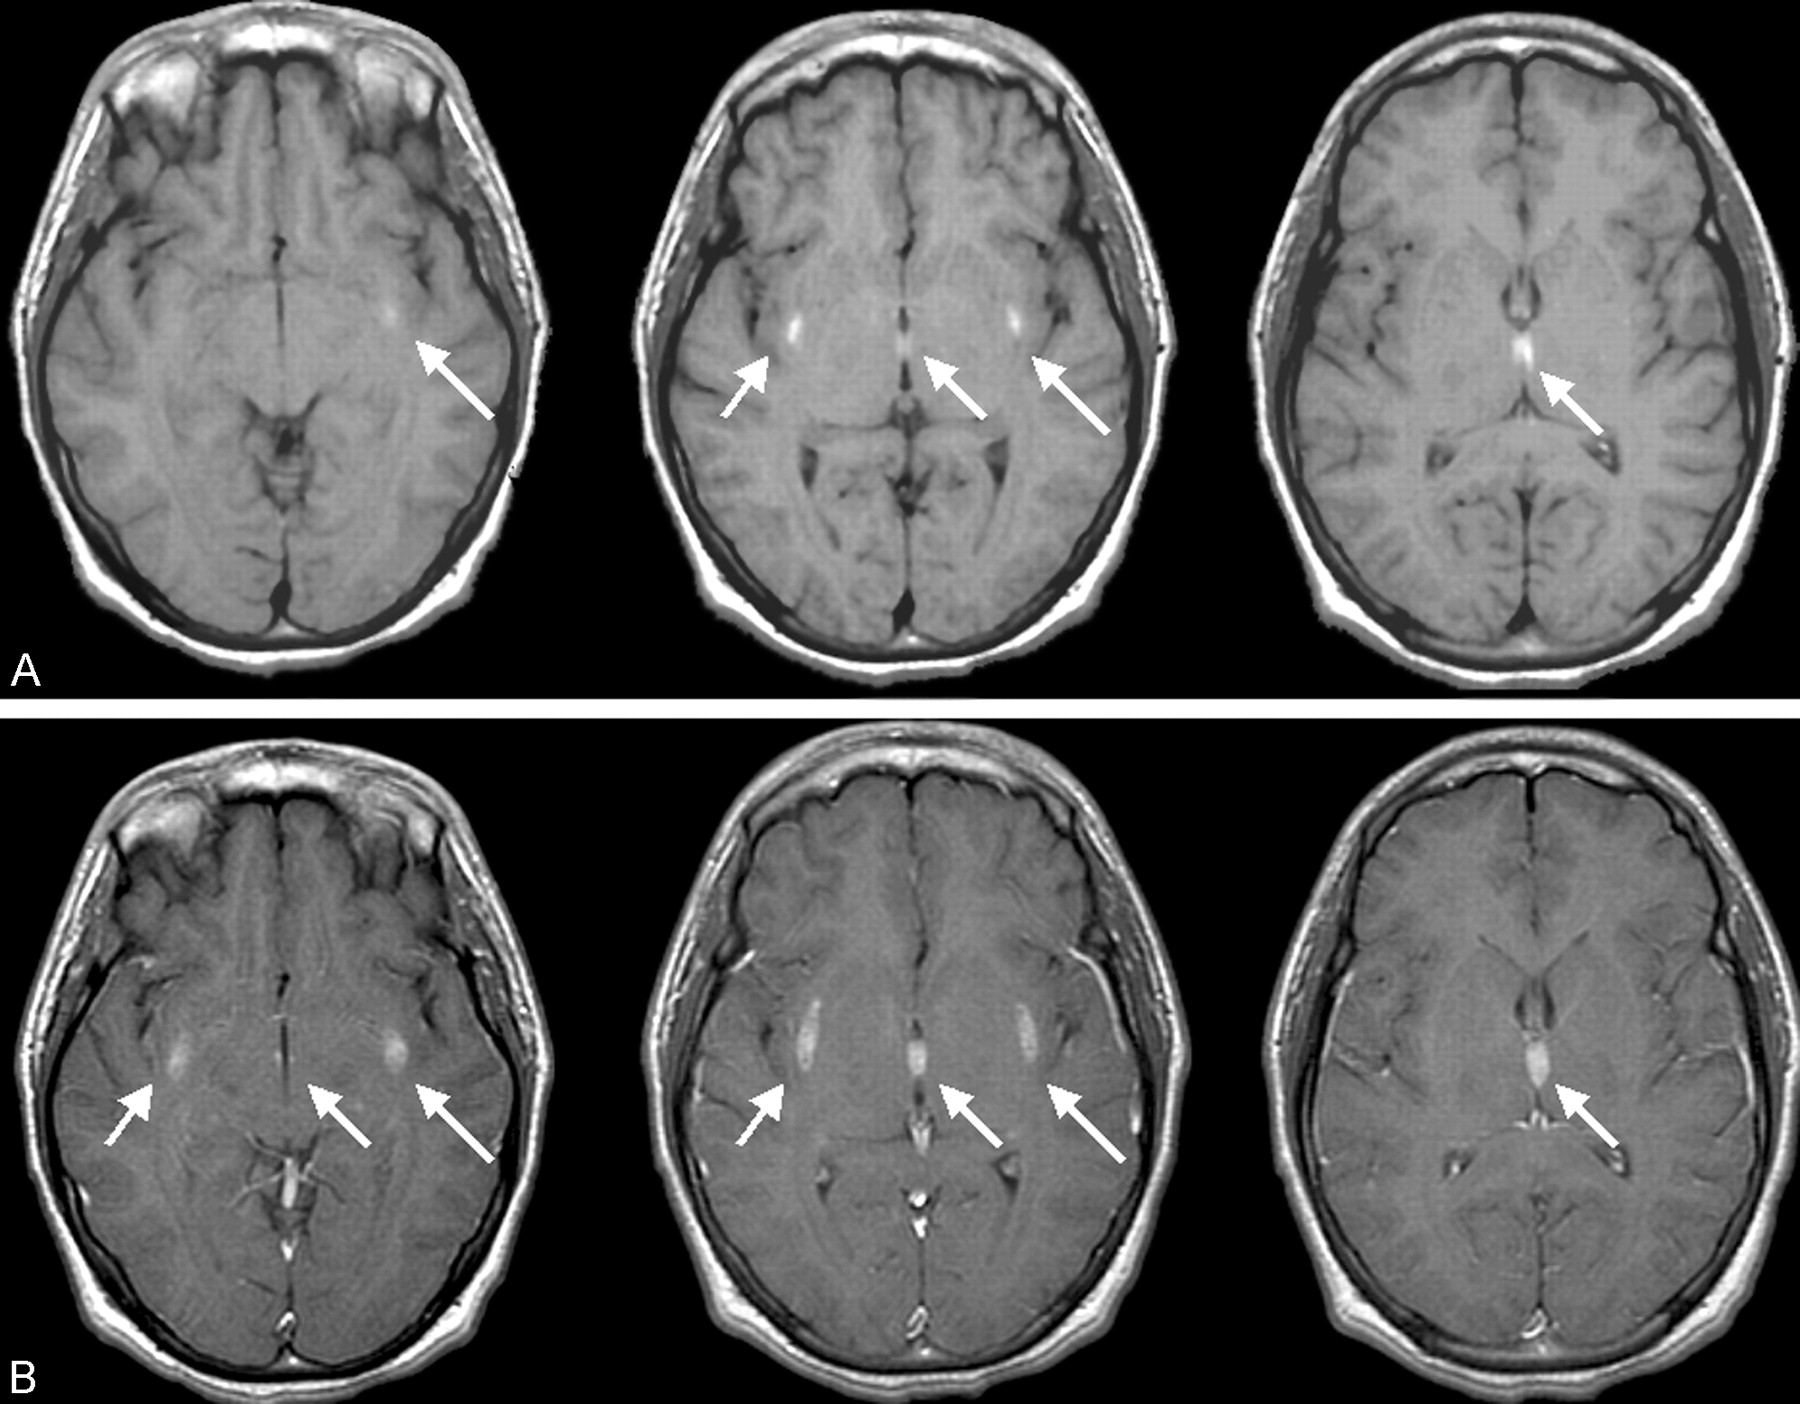

MR imaging of the brain was therefore performed. Proton density–and T2-weighted images revealed hyperintensity of the external capsules and adjacent lateral putamen, the paraventricular nucleus of the thalamus, and scattered areas throughout the cerebellar hemispheres (Fig 1). Pre- and postcontrast T1-weighted images demonstrated T1 shortening and accompanying enhancement only in the supratentorial lesions (Fig 2). T1 shortening in the paraventricular nucleus of the thalamus bordering the third ventricle also extended into the third ventricle, suggesting an underlying hemorrhagic cause, resulting from extracellular methemaglobin (Fig 2). Areas of T2-weighted changes in the cerebellum had corresponding darkness on T1-weighted images but were also noted to enhance after contrast medium administration (Fig 3). These findings suggest an ischemic and hemorrhagic small vessel process, both supra- and infratentorial.

Axial postcontrast T1-weighted image shows scattered cerebellar hyperintensity and patchy enhancement in the cerebellar hemispheres bilaterally (arrows).

It is of interest that, in the cerebellum, thermal injury itself may cause destruction of the Purkinje cells. Increased production of heat shock proteins within the rabbit cerebellum during hyperthermia indicates that Purkinje cells may have an increased demand for thermal injury repair. Therefore, in addition to being susceptible to hypoxic-ischemic injury, there is evidence that Purkinje cells are also susceptible to direct thermal injury (6).

Although heat can affect all organ systems adversely, it is known that the cerebellum is especially susceptible (1). The Purkinje cells within the cerebellum are, in particular, vulnerable to thermal injury. As noted above, it has been suggested the hyperthermia itself, as opposed to the resultant hypoxic or ischemic insults, causes the destruction of Purkinje cells (1, 6). This neuronal destruction then causes generalized cerebellar atrophy, which has been widely reported as evidenced by MR imaging (1, 3, 7); however, to our knowledge no reports of bilateral signal intensity alterations and enhancement of the cerebellum exist in the literature. This suggests that, in addition to the likely ischemic and hemorrhagic small vessel process seen supratentorially, we are also seeing it infratentorially. Hyperintensity on both T1- and T2-weighted images of the cerebrospinal spaces of the third ventricle also suggests an ischemic and hemorrhagic mechanism, implying spread of intracellular methemoglobin into the third ventricle from adjacent hemorrhagic infarction (Figs 1 and 2).

The present case demonstrates a unique new finding of symmetric hyperintensity in the external capsules and thalami, an unusual pattern not previously described in the setting of heat stroke. The presence of specific subacute enhancing T2-weighted signal intensity abnormalities in the cerebellum has also not been previously described and is likely the precursor of the reported long-term sequelae of cerebellar atrophy. The enhancement reflects a breakdown of the blood-brain barrier. As stated above, the physiology of heat stroke includes increased intracranial pressure combined with autonomic dysfunction that lead to cerebral hypoperfusion and ischemia and a tendency toward intracranial hemorrhage because of abnormal coagulation. We propose that these known physiologic effects of heat stroke are the underlying causes for the supratentorial findings. The cerebellar findings may be a combination of these factors coupled with or solely due to the directly destructive effects of hyperthermia on the Purkinje cells.